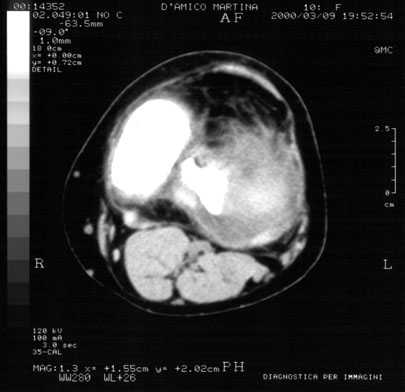

fig.1